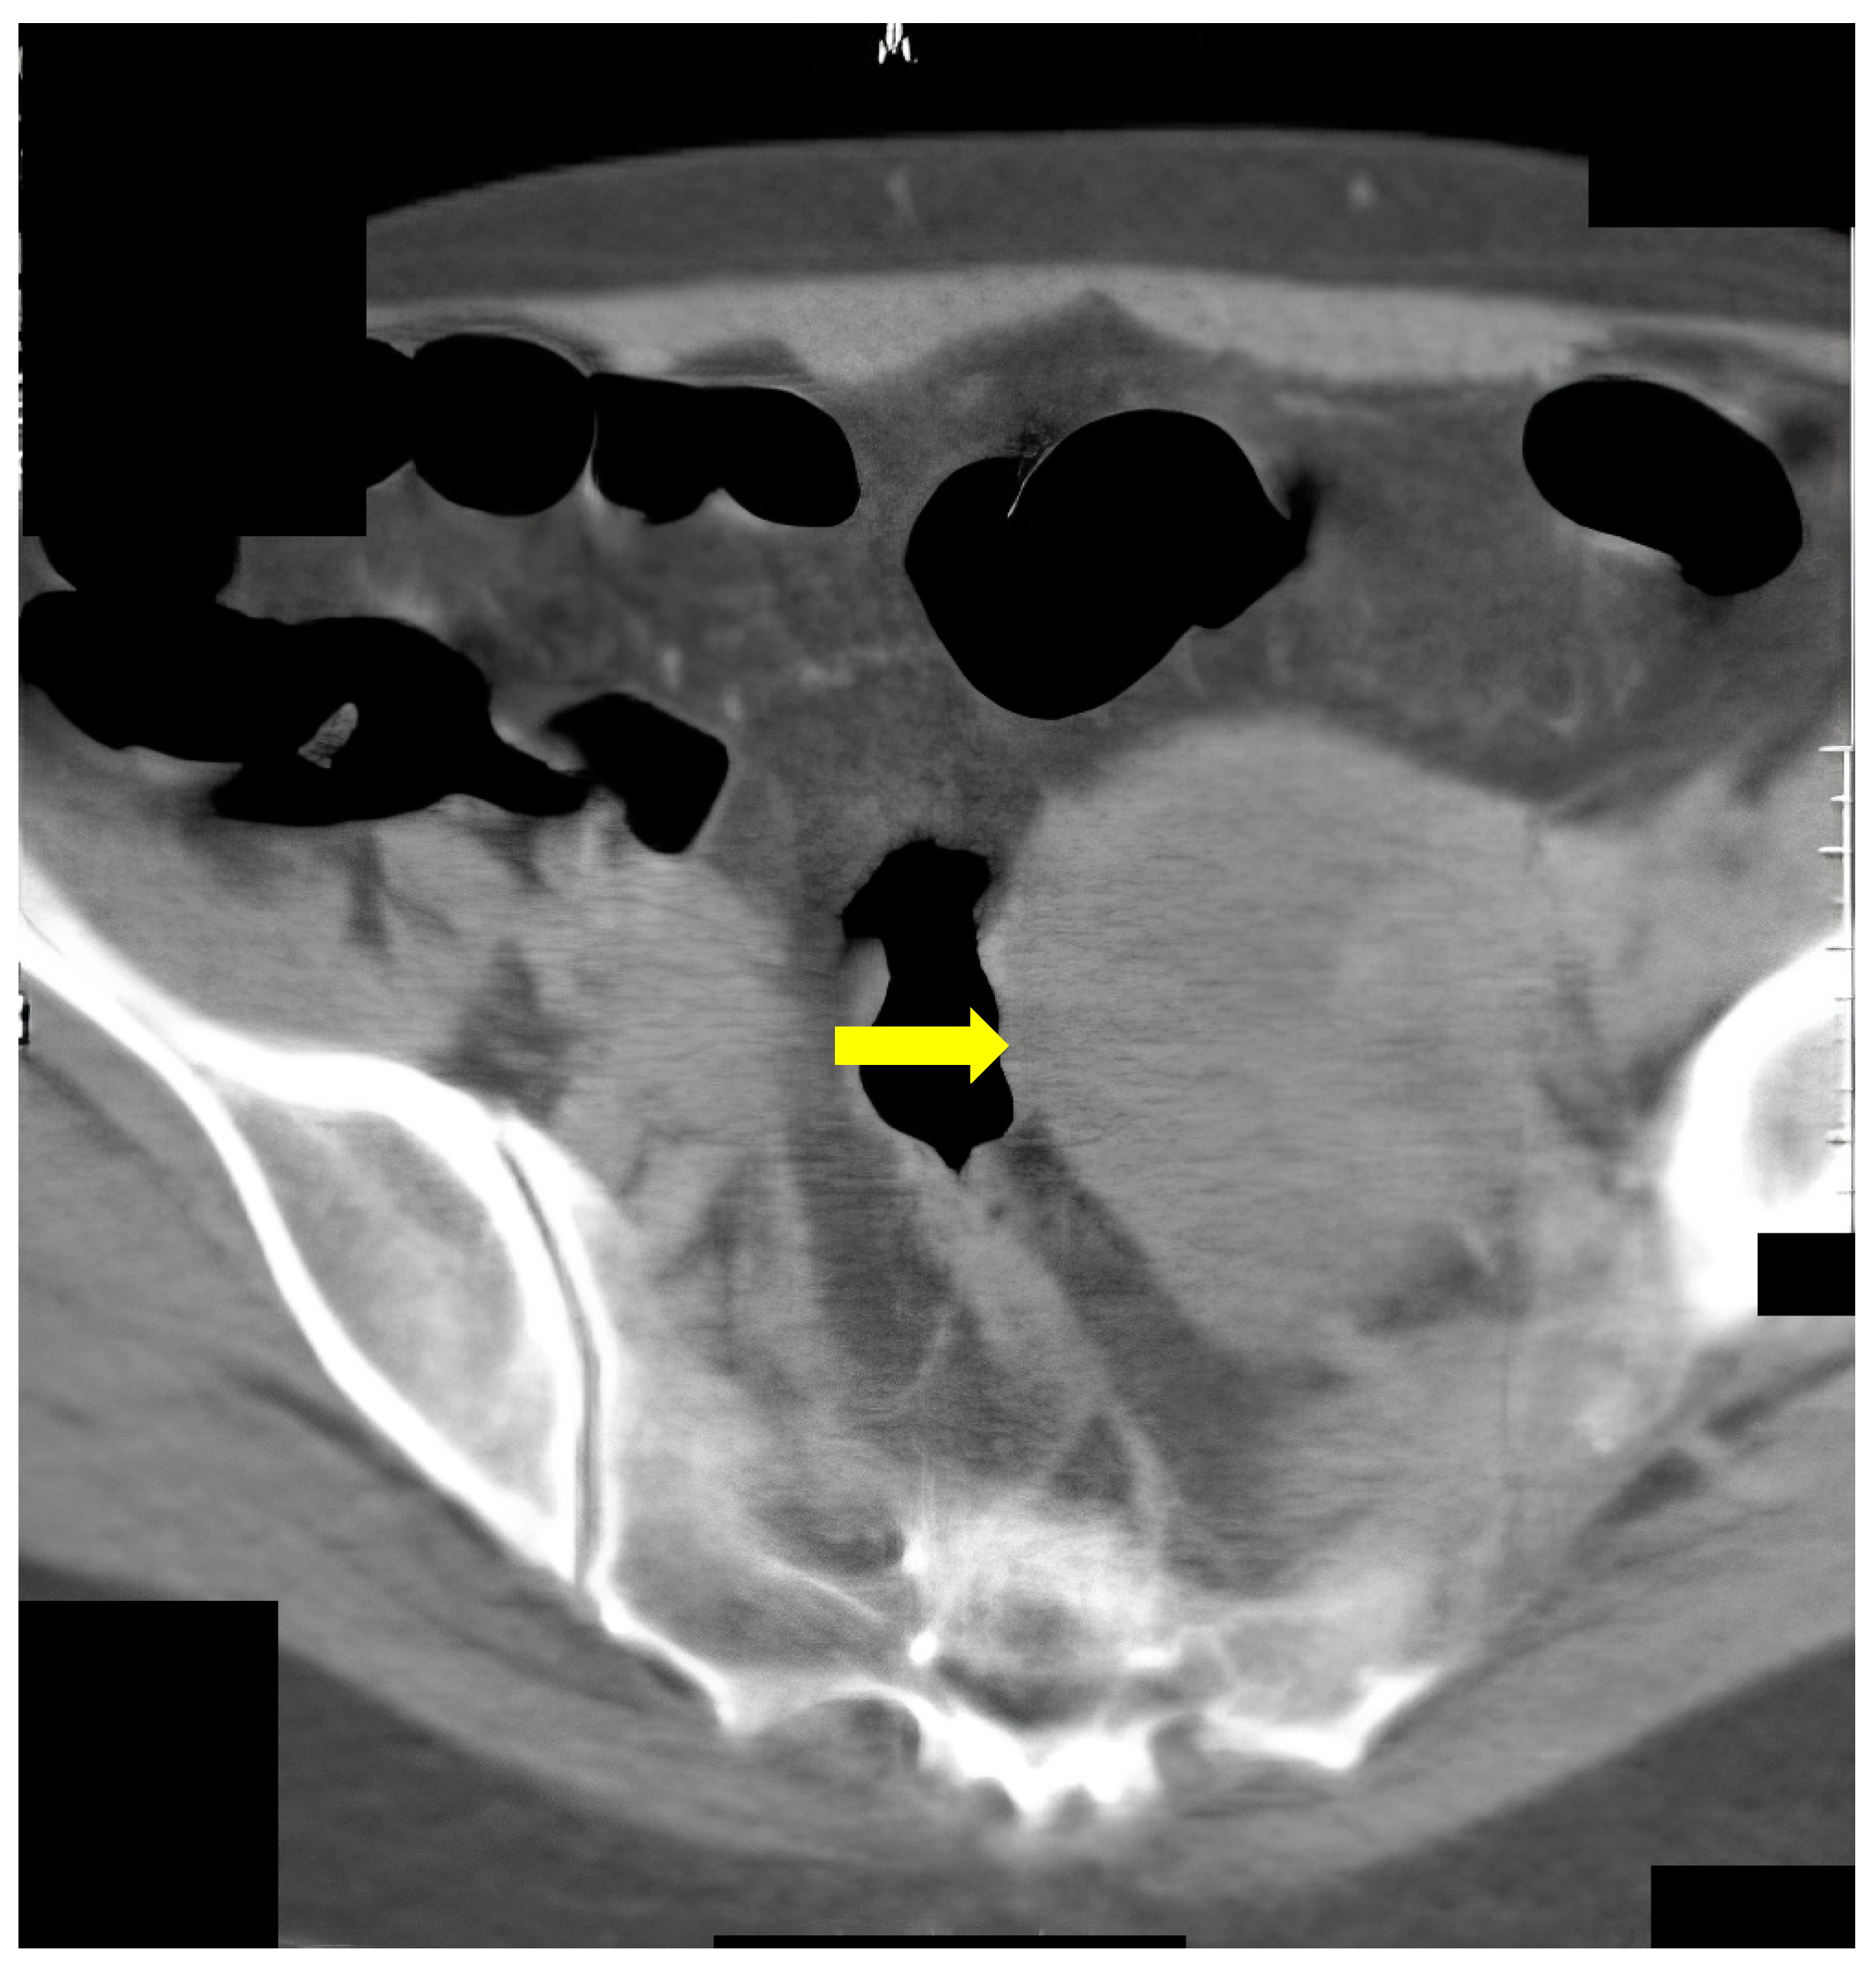

Figure 5 shows a 67-year-old female with flank pain and transitional spasm. The clinical data suggested intestinal tumors. FCS was performed, and there was evidence of extraluminal formation, compressing the colon. Afterward, CT colonography was performed, on which tumor formation arising from the left ovary was observed.

Figure 5.

CT colonography–axial slice in a supine position. Narrowing of the sigmoid colon due to a large ovarian tumor in the left is presented (yellow arrow). FCS did not detect any abnormalities.